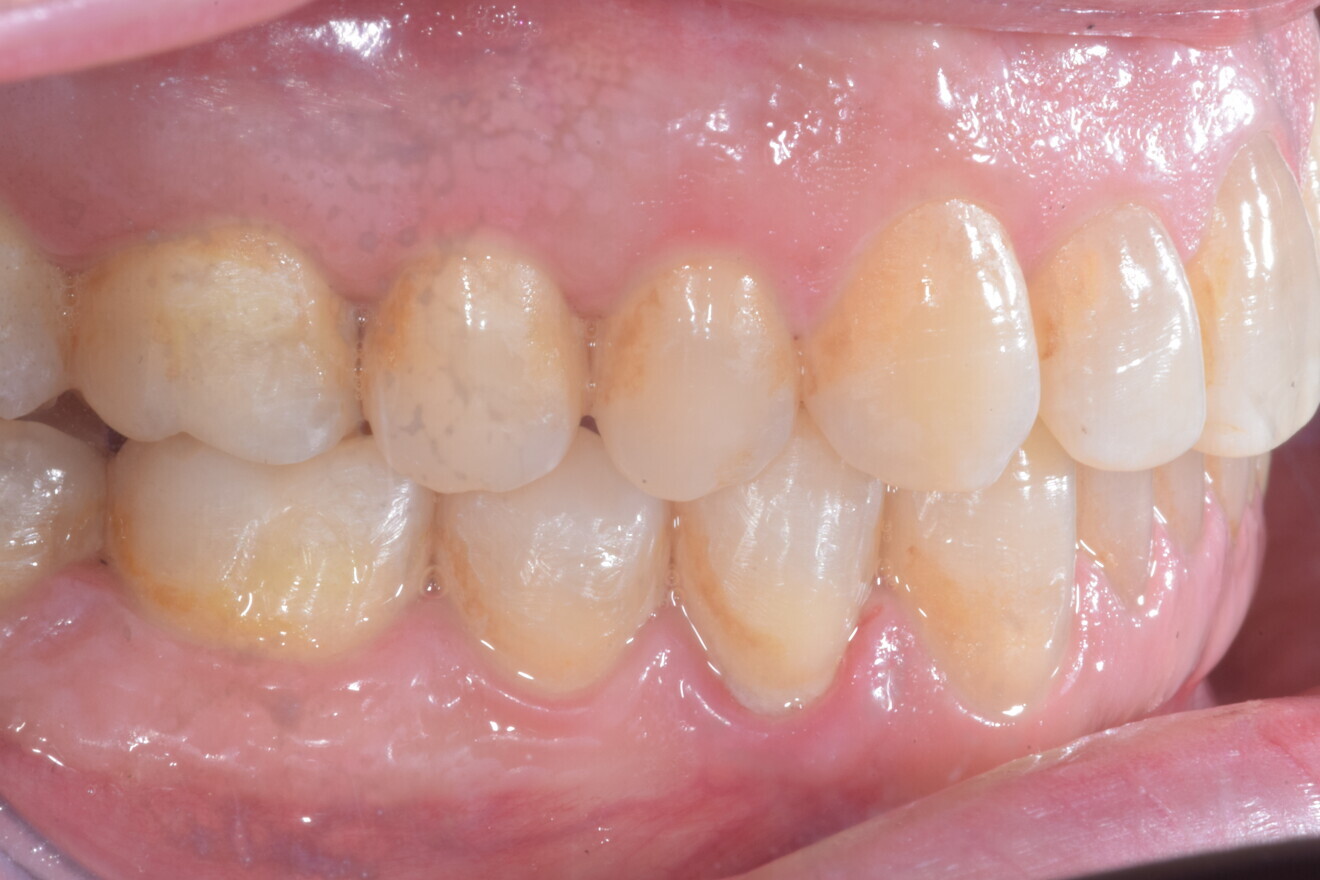

A 37-year-old male patient presented with the chief need for re establishing anterior alignment in both arches. Facial analysis showed a short face with a flat profile but proper chin projection (Figs. 9–12), and clinical examination revealed a skeletal Class I (ANB = 0.89°) and dental Class I malocclusion with severe deep bite (almost 100%), a deep curve of Spee, normal maxillary central incisor torque (Ui–FH = 110°), mild maxillary crowding and moderate mandibular crowding (Figs. 13–18). The deep bite components were represented in this patient by the severe skeletal condition of hypo divergent pattern (FMA = 14.24°) with normal maxillary and mandibular incisor inclination and decreased gonial angle (110.46°). Analysis of the cephalometric radiograph indicated a reduced lower anterior facial height, combined with a hypo-divergent pattern (Fig. 19). The only treatment option suggested was orthodontic treatment with aligners for deep bite correction with all the features described (bite ramps, pressure area, 3D curve of Spee levelling, Class II elastics and heavy occlusal contacts).

Fig. 13

Fig. 14

Fig. 15

Fig. 16

Fig. 17

Fig. 18